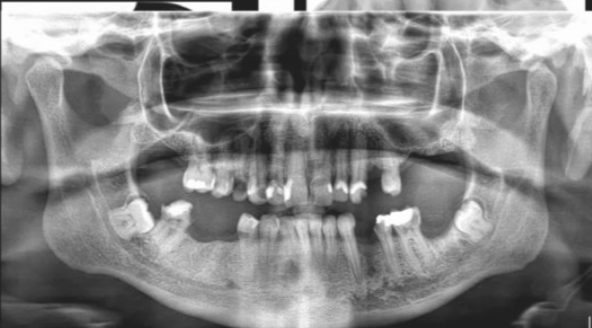

when may we consider an OPG when assessing periapical inflamm pathology?

when periapical already taken and lesion not demonstrated v well, so we may want a larger view

or it may be a dose benefit for a pt with grossley decayed teeth